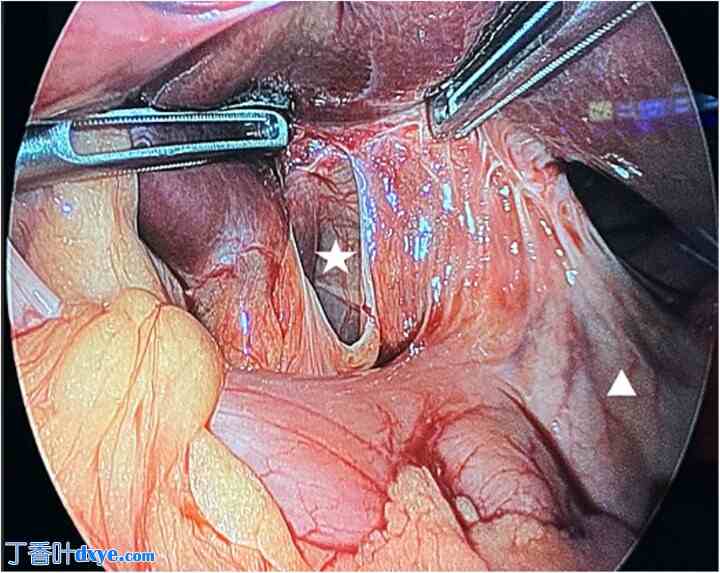

患者被紧急送往手术室进行诊断性腹腔镜检查。术中发现一小肠袢通过小网膜缺损处疝出。进一步检查后发现,缺损位于肝胃韧带而非温斯洛孔(图2)。疝出的肠管被释放。肠管看似出血,但仍可存活。因此,认为无需切除。随后,在腹腔镜下使用间断缝合关闭缺损,以防止复发。患者术后恢复顺利,并于术后第三天出院。

图2

术中发现。小网膜缺损(白色星号)。胃(白色三角形)。